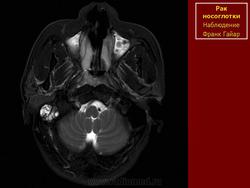

ЛОР. Онк. Рак носоглотки. +

Рак носоглотки